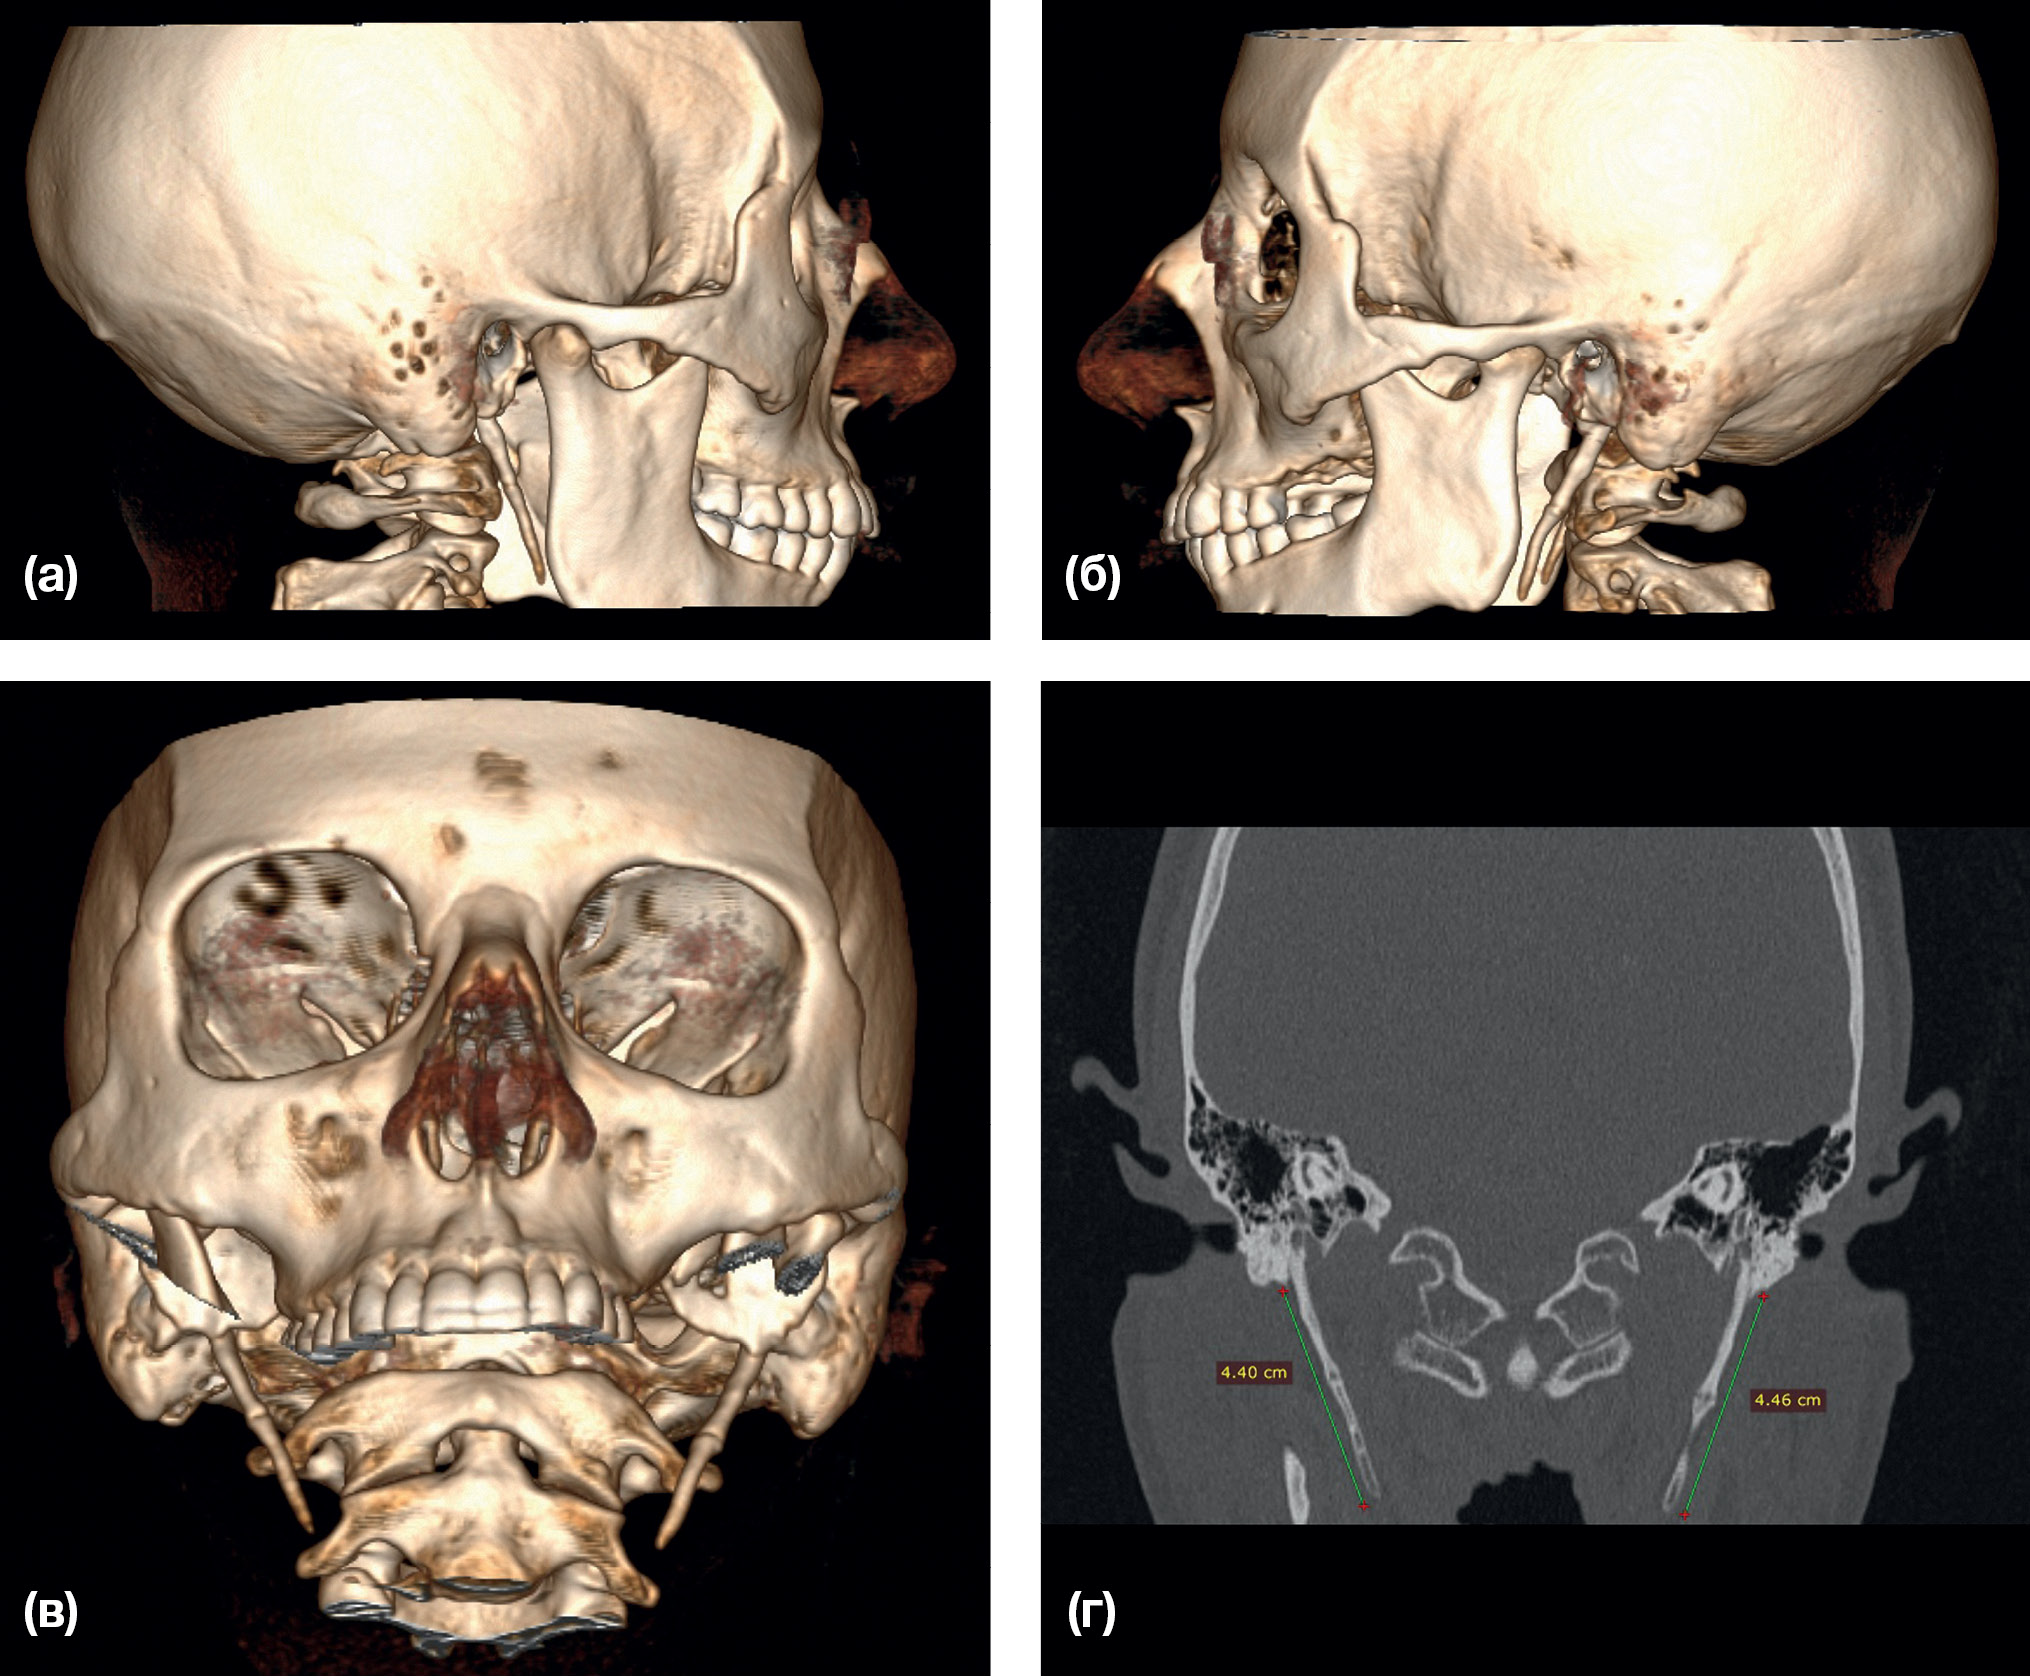

Рис. 4. Компьютерная томография пациентки М., 32 года. Диагноз: Аномалия развития шиловидного отростка височной кости с двух сторон

Примечание. (а) — 3D-реконструкция, фас; (б) — коронарный срез.